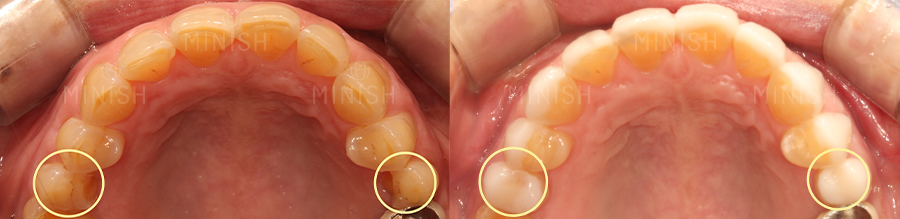

● 질환: 어금니깨짐, 교모, 마모, 에나멜 비박화

● 촬영일자: Before 2022.03.01 After 2022.03.08

● 치료기간: 1주

상악 (윗니)

천안엄마 박OO님은 전치부 문제뿐 아니라 음식을 제대로 씹을 수 없을 만큼 어금니깨짐도 심각한 상태였습니다. 이 부분은 어금니 미니쉬로 개선하였는데요. 어금니 미니쉬 역시 에나멜과 가장 비슷한 미니쉬를 사용하여 잇몸, 울퉁불퉁한 씹는 면까지 정밀하게 코팅해주었으며 다시금 건강한 어금니로 음식을 잘 씹을 수 있게 되었습니다.

하악 (아랫니)

또한 삐뚤빼뚤했던 아랫니의 치아 배열도 개선되기를 바라셨는데요. 전치부 치아가 많이 닳고(교모) 손상의 범위가 넓었기 때문에 듀얼미니쉬로 개선이 진행되었습니다. 치아의 전면뿐 아니라 혀 안쪽의 설면까지도 세밀하게 치아코팅하여 재건 및 보호할 수 있게 되었습니다. 위 사진에서도 보실 수 있듯이 제각기 달랐던 배열이 고르게 개선되고, 닳았던 부분들을 코팅해주어 건강하게 바뀐 것이 보이시죠?